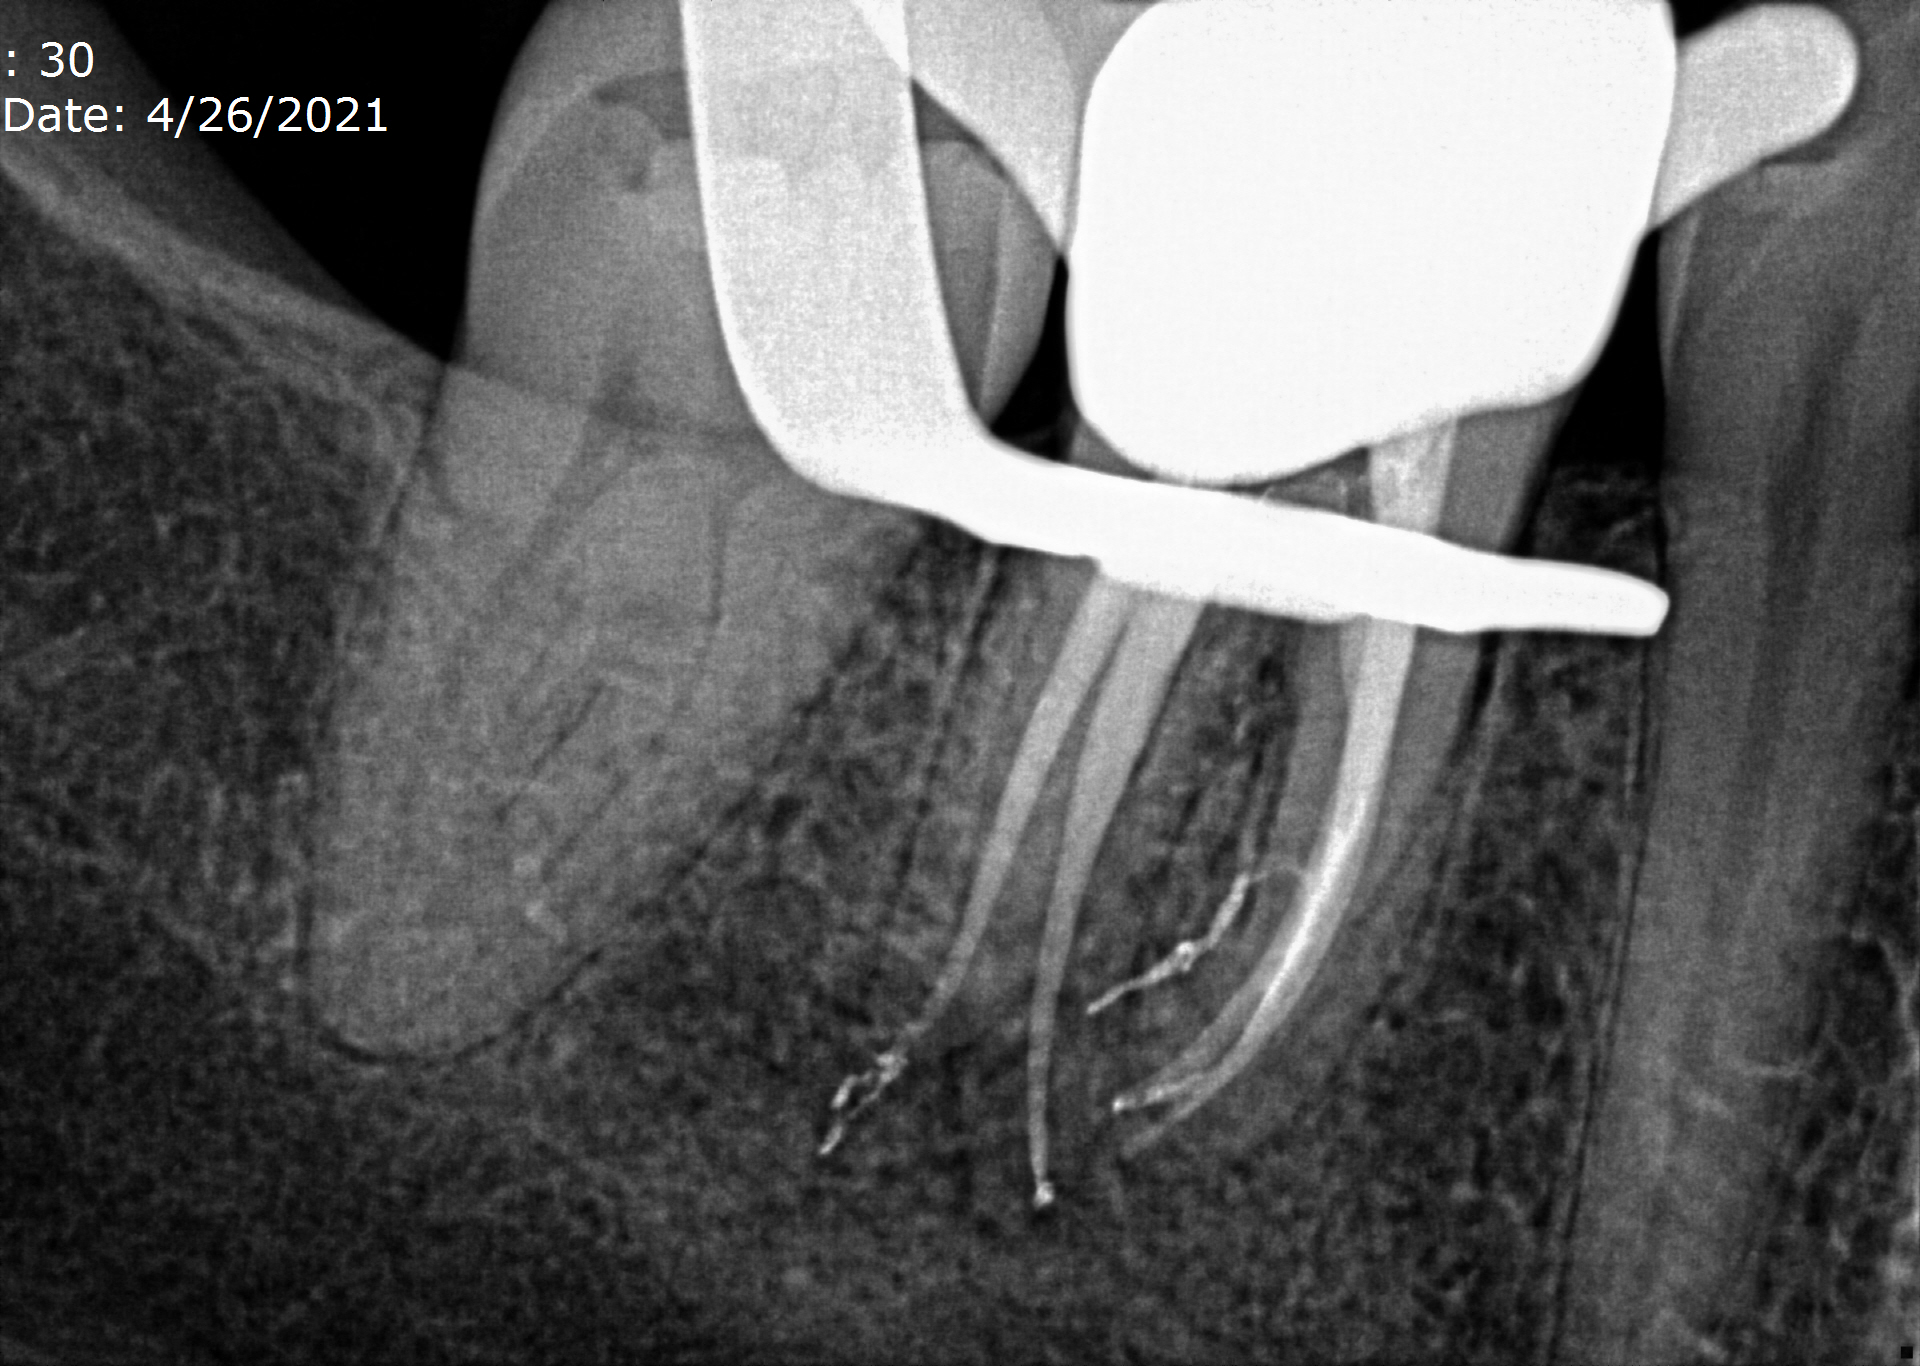

Periapical radiographs before, during,and after endodontic treatment of Endodontic Treatment Emphysema Presented here is a case of subcutaneous emphysema that occurred after sodium hypochlorite irrigation during. A review of the literature. The use of three way air syringe and forceful irrigation of root canal can lead to surgical emphysema of subcutaneous tissue planes in. Surgical emphysema is most often associated with use of an air rotor dental handpiece and most commonly. Endodontic Treatment Emphysema.